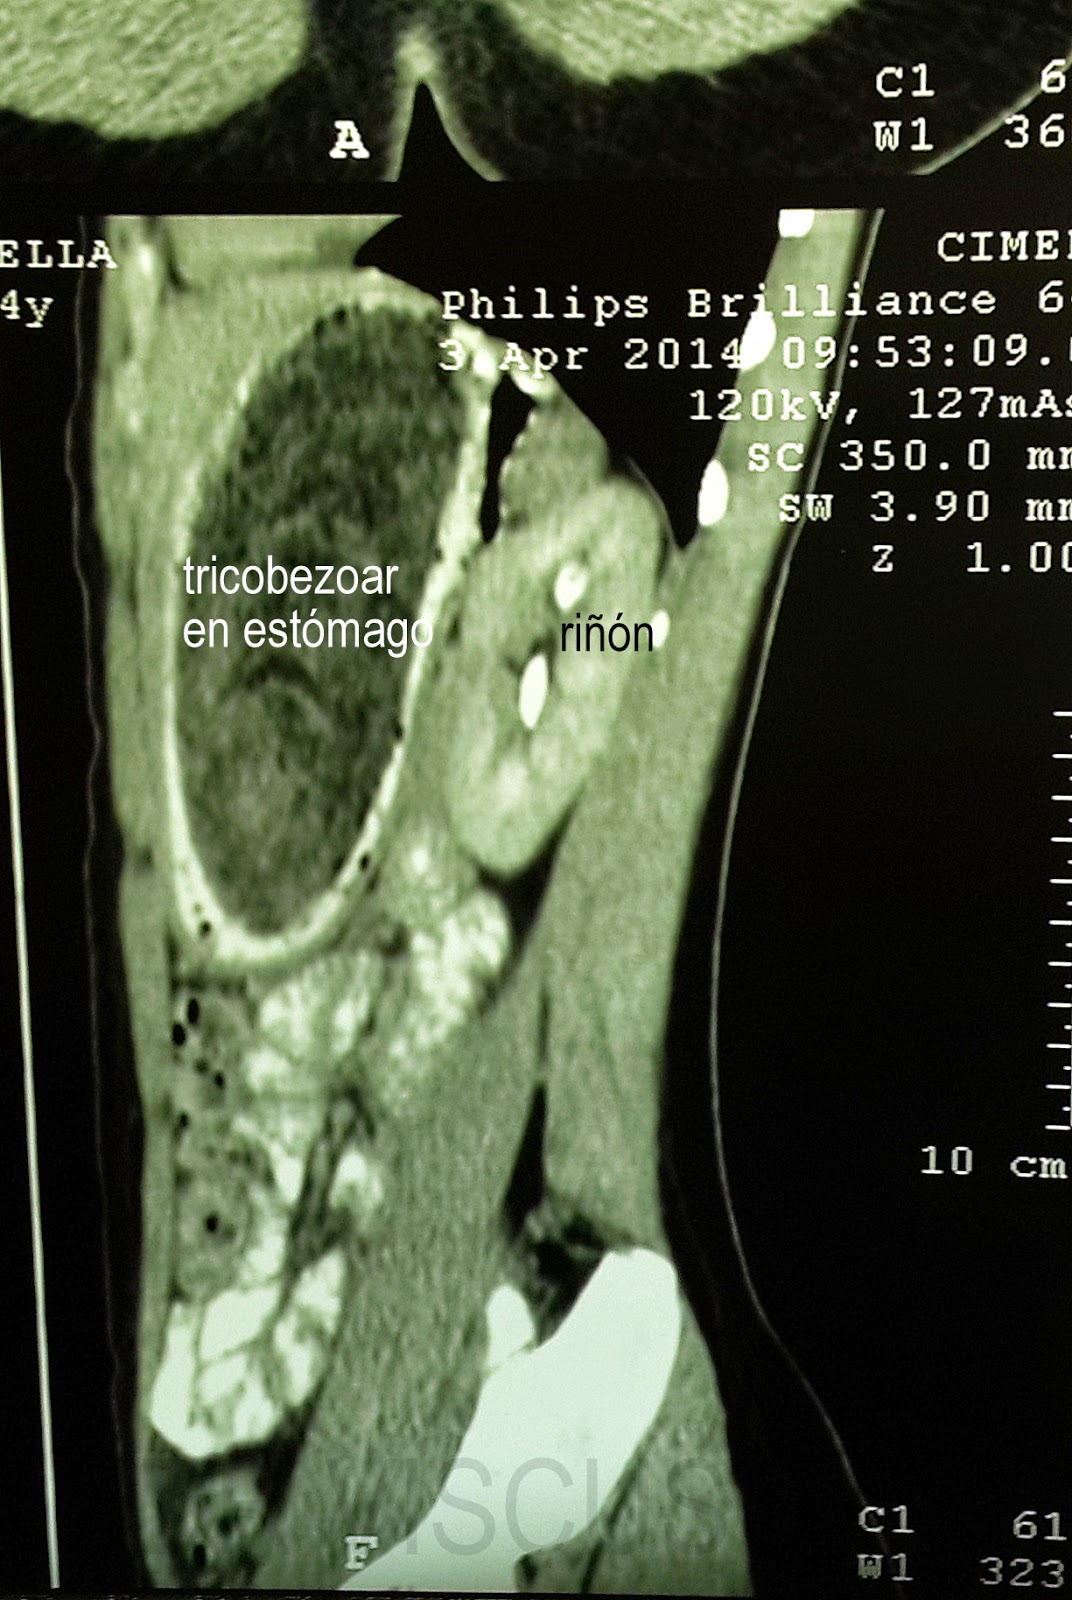

tac perfil

Se confirmo el diagnóstico por gastroscopía, de tricobezóar (masa de cabellos ingerida por la paciente durante muchos meses, y se intentó la fragmentación y extracción endoscópica. Esto no se logró por lo compacto de la masa de pelos. Es operada extrayéndose un gran molde del estómago formado por cabello.

foto1: tac corte transversal